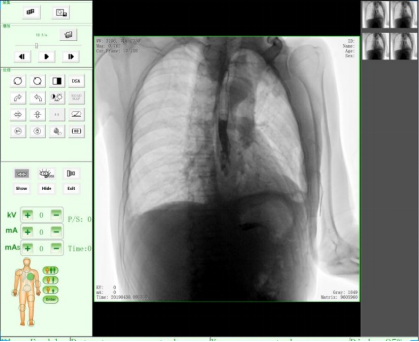

動(dòng)態(tài)DR17*17英寸非晶硅動(dòng)態(tài)平板探測(cè)器,透視像素達(dá)200萬,可實(shí)時(shí)顯示大幅面高清拍攝視野。適用于全身各部位攝影,包括常規(guī)攝影,如胸片、頸椎、腰椎、腹部、頭顱、四肢等,以及特殊攝影。

適用于全身各部位的透視檢查及輔助治療,如隱匿性肋骨骨折、胸透檢查、骨折復(fù)位、小兒腸套疊空氣灌腸等。同時(shí)具備多種幀率透視模式,影像更加流暢、準(zhǔn)確。